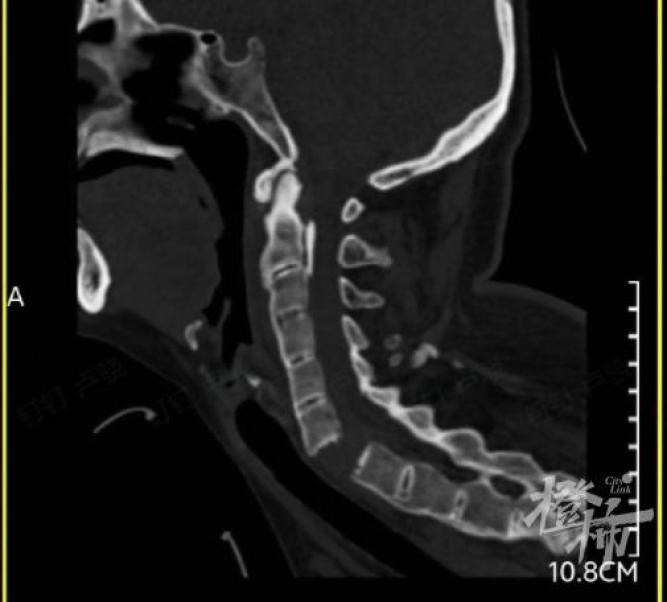

当时,刘女士患有颈部疼痛和四肢无力,然后发现她不能全身活动。随后,她被紧急送往附近的医院治疗。经颈椎影像检查,发现刘女士完全断开了6-7个颈椎,颈椎骨折造成颈髓损伤,导致全身瘫痪。

(发现刘女士的颈椎完全断裂)